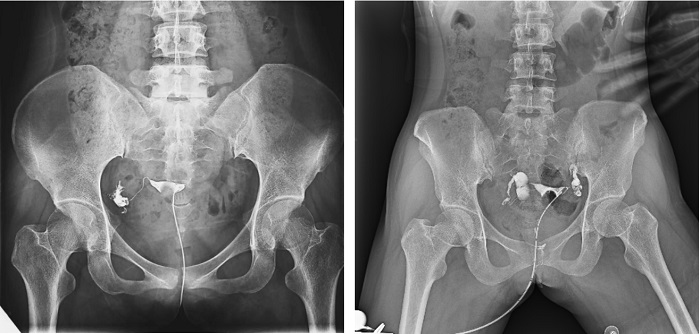

子宮輸卵管造影檢查損傷小,準確率高,是婦科檢查的常用方法。利用動態(tài)DRF進行子宮輸卵管造影檢查,大大超越了過去的檢查技術,更加精準高效。動態(tài)DRF矩形采集面積大,一次曝光即可顯示整個盆腔,大幅減少觀察時間,可控的瞬時照射避免受檢者吸收過多X線,對育齡期女性檢查尤為重要??稍谠煊皠┝鲃拥倪^程中完成拍片,抓拍到關鍵圖像,幫助醫(yī)生更加清楚地了解到管腔的具體通暢情況及堵塞部位,提高診斷的精準性。

▲輸卵管造影

普利德動態(tài)平板DRF床體智能化程度更高,在進行子宮輸卵管造影檢查時,醫(yī)生可以通過調(diào)整床體起倒角度精準控制造影劑的流動方向和速度,并根據(jù)造影劑在輸卵管及盆腔里的顯影準確判斷輸卵管堵塞部位、程度及性質(zhì),極大提高了拍片效率和診斷的精準性。